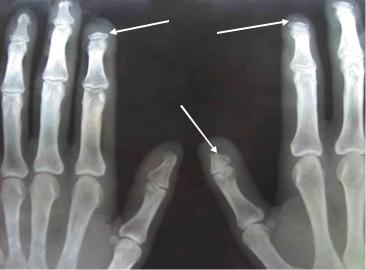

Уплотнение кожи(склеродермия всегда начинается с пальцев кистей (склеродактилия)(рис.5-1). Выраженность уплотнения кожи оценивается пальпаторно по 4-балльной системе: 0 - уплотнения нет; 1 — незначительное уплотнение; 2 — умеренное уплотнение; 3 — выраженное уплотнение (невозможно собрать в складку). Для объективизации поражения кожи определяется кожный счѐт, который представляет сумму балльной оценки выраженности уплотнения кожи в 17 анатомических областях: на лице, груди, животе и на симметричных отделах конечностей

— пальцах, кистях, предплечьях, плечах, бѐдрах, голенях и стопах. При ССД отмечается стадийность поражения кожи: отѐк, индурация, атрофия. Выраженность уплотнения кожи различается между отдельными больными и достигает максимума в первые 3 — 4 года болезни. Кожный счѐт коррелирует с висцеральной патологией и является одним из предикторов неблагоприятного исхода ССД.

Наличие зоны некроза, как следствие длительно существующего феномена Рейно

Рис. 5-1. Склеродактилия, сгибательные контрактуры пальцев.

Акроостеолиз— резорбция концевых отделов дистальных фаланг кистей вследствие длительной ишемии, проявляется укорочением и деформацией пальцев. В некоторых случаях наблюдается рассасывание дистального отдела лучевых костей и отростков нижней че люсти (рис.5-4).

Рис. 5-4. Остеолиз дистальных фаланговых костей.